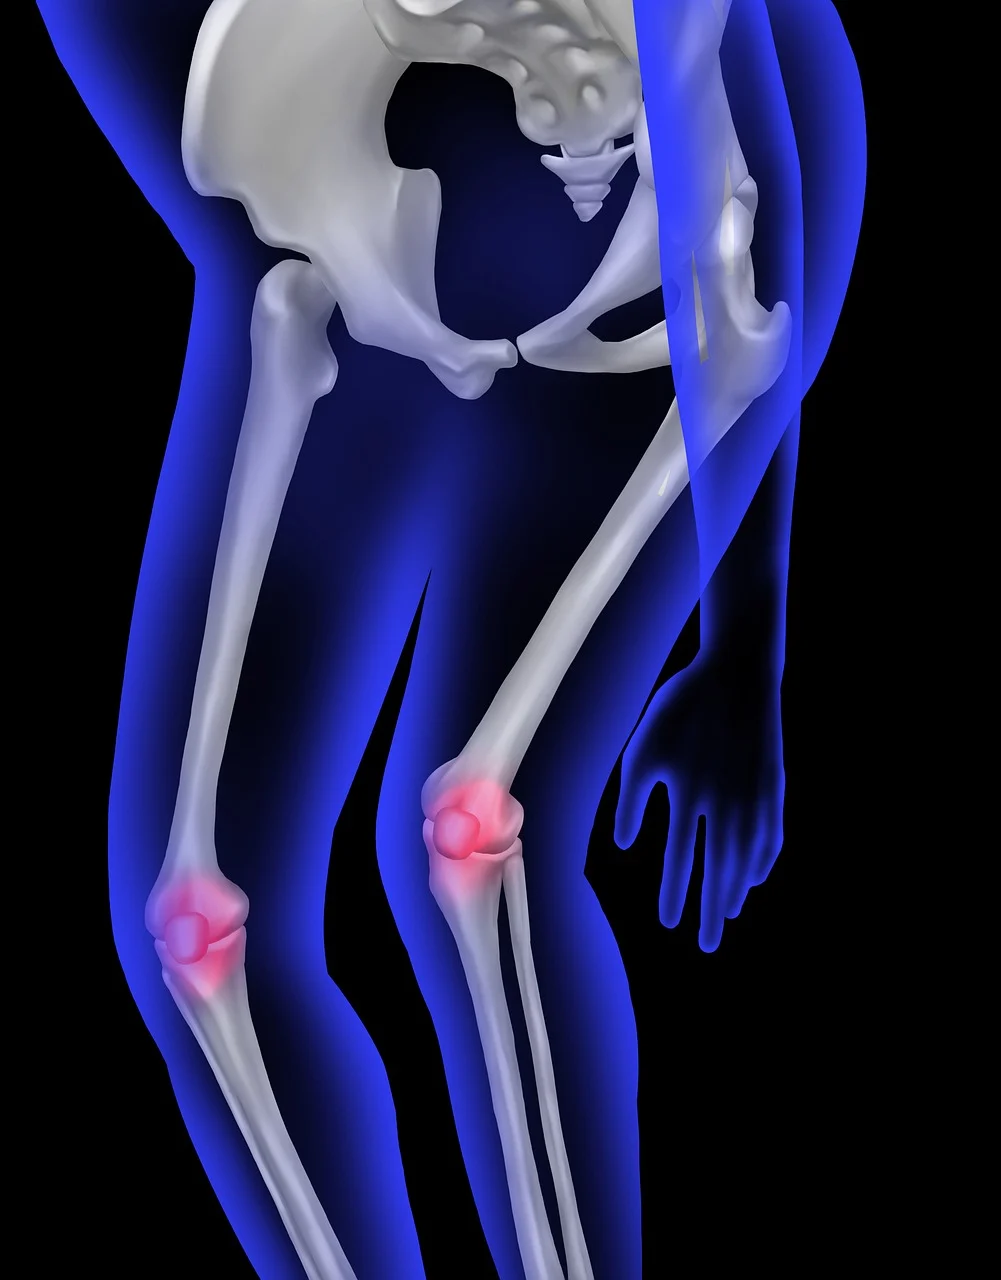

초기에는 거의 증상이 없어 침묵의 질환이라고 불리지만, 골절 위험이 높아지면서 다음과 같은 신호가 나타난다.

- 작은 충격에도 골절

- 허리·등 통증

- 키가 줄거나 등이 굽음

- 손목·고관절 골절

- 골절 후 회복이 느림

골다공증이 있으면 작은 충격에도 골절 위험이 높다.

실생활에서 다음을 유의하면 골절 예방에 도움된다.